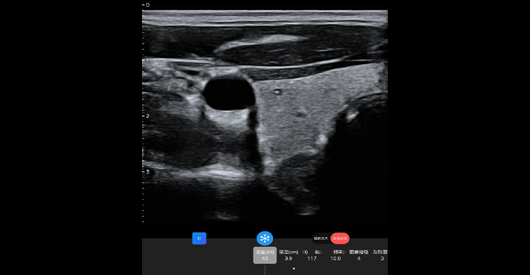

臂丛神经

探头类型:线阵探头。典型场景:血管、小器官。

甲状腺短轴

阵元基数:128。信号通道:64。